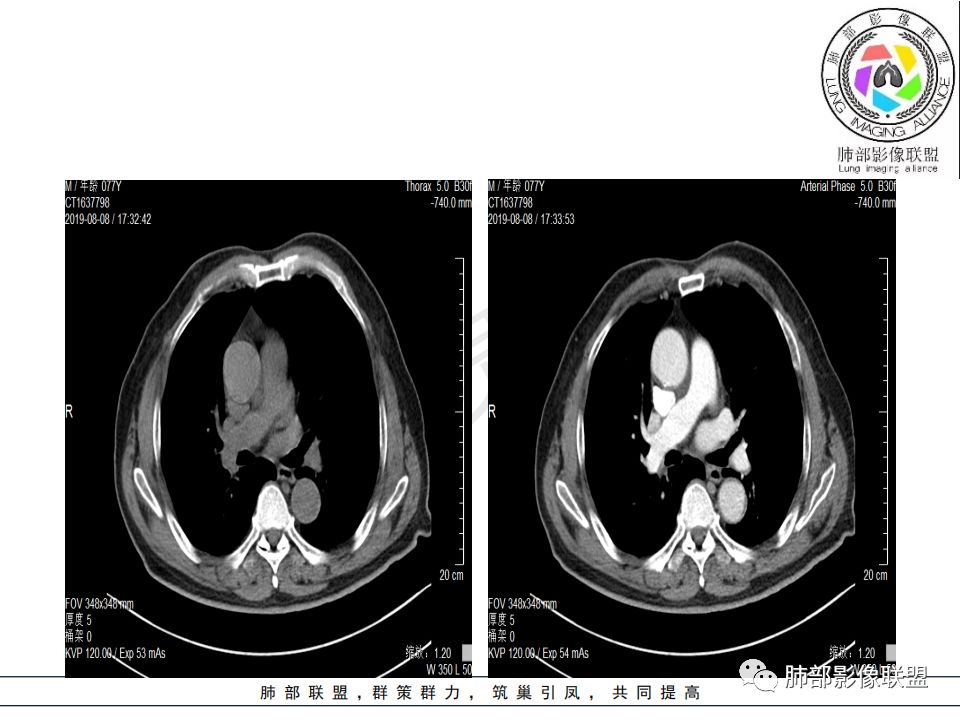

影像:影像右侧大支气管阻塞,临床没有症状或很轻微,要想到胃腺癌转移;胸壁代偿好,透亮度稍低不明显,慢性过程;34.8-52.5HU,主病灶支气管前壁另有1结节,都做成增强两期了,动脉期较平扫有强化;

晨读:患者老年男性,以咳嗽一月就诊,少量白痰,胸CT:纵隔右移,右肺体积缩小,气管下段管壁可见结节样改变,气管软骨变形,气管下段及右主支气管可见新生物向管壁浸润,并向管腔外生长,右上肺肺不张,但不张边缘可见病灶呈膨胀性生长,可见分叶,增强后强化明显。考虑:肺部恶性病变(鳞癌?)

右肺上叶肿块,边缘光滑,略膨隆,近段支气管堵塞,平扫密度均匀,增强后不均匀强化,其内可见不规则血管和坏死,纵隔淋巴结肿大,老年男性,无感染性病史,综合考虑恶性肿瘤(鳞癌,腺癌),鉴别:OP(一般下叶多见)

从强化情况和冠状位看主要还是从外向内的一个肿块,有不张,但不张范围不大,近端支气管堵塞,考虑腺癌或类癌(原发或转移都可能),鉴别鳞癌。

@曹坤,河北保定清苑区人民医院ct室 肿块大,阻塞和不张范围小,强化这么大肿块没有明显坏死,鳞癌这样相对少见了

@刘鋆(福州长乐区医院)影像科 转移啊,腔外都在生长,部分通过支气管壁进入腔内

@刘鋆(福州长乐区医院)影像科 先转移生长到外面,然后进入腔内生长,也是外朝内一种,与平时那种外朝内生长逐渐侵犯近端气管没有太多区别,只不过这个是转移而已。